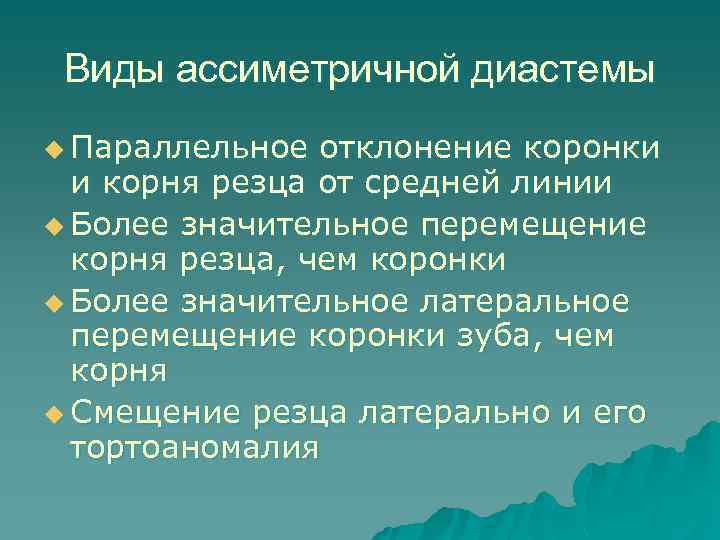

Виды ассиметричной диастемы u Параллельное отклонение коронки и корня резца от средней линии u Более значительное перемещение корня резца, чем коронки u Более значительное латеральное перемещение коронки зуба, чем корня u Смещение резца латерально и его тортоаномалия

Виды ассиметричной диастемы